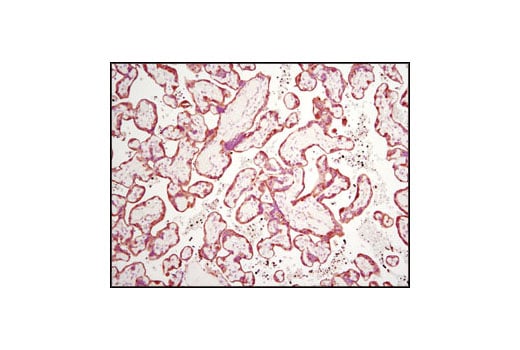

Immunohistochemical analysis of paraffin-embedded human placenta using TGM2 (D11A6) XP® Rabbit mAb.

Immunohistochemistry Image 2: TGM2 (D11A6) Rabbit Monoclonal Antibody